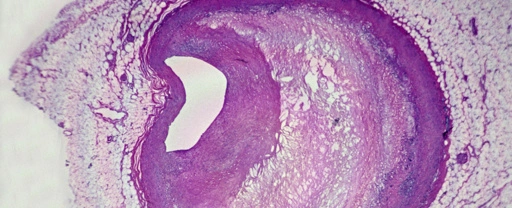

Plastic Discovered In More Than 50% of Plaques From Clogged Arteries

Plastic Discovered In More Than 50% of Plaques From Clogged Arteries

Plastic Discovered In More Than 50% of Plaques From Clogged Arteries

Plastic Discovered In More Than 50% of Plaques From Clogged Arteries

Plastic Discovered In More Than 50% of Plaques From Clogged Arteries